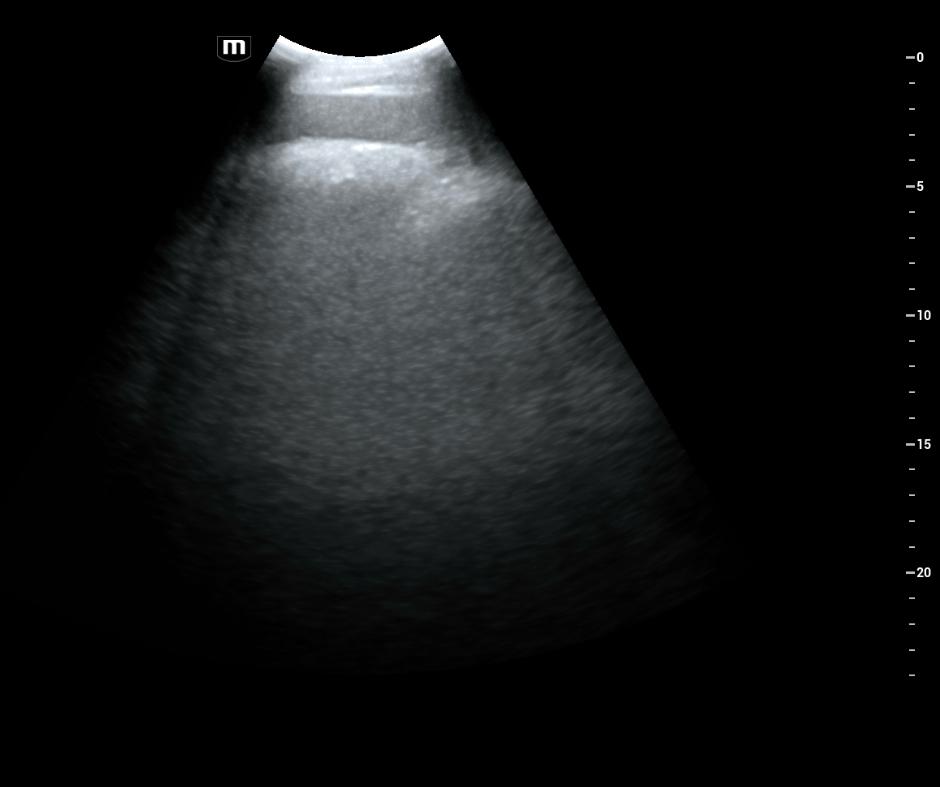

Weiterführende Untersuchungen: Ultraschall

Mithilfe des Ultraschalls konnten wir vermehrt Sandablagerung im Dickdarm nachweisen.